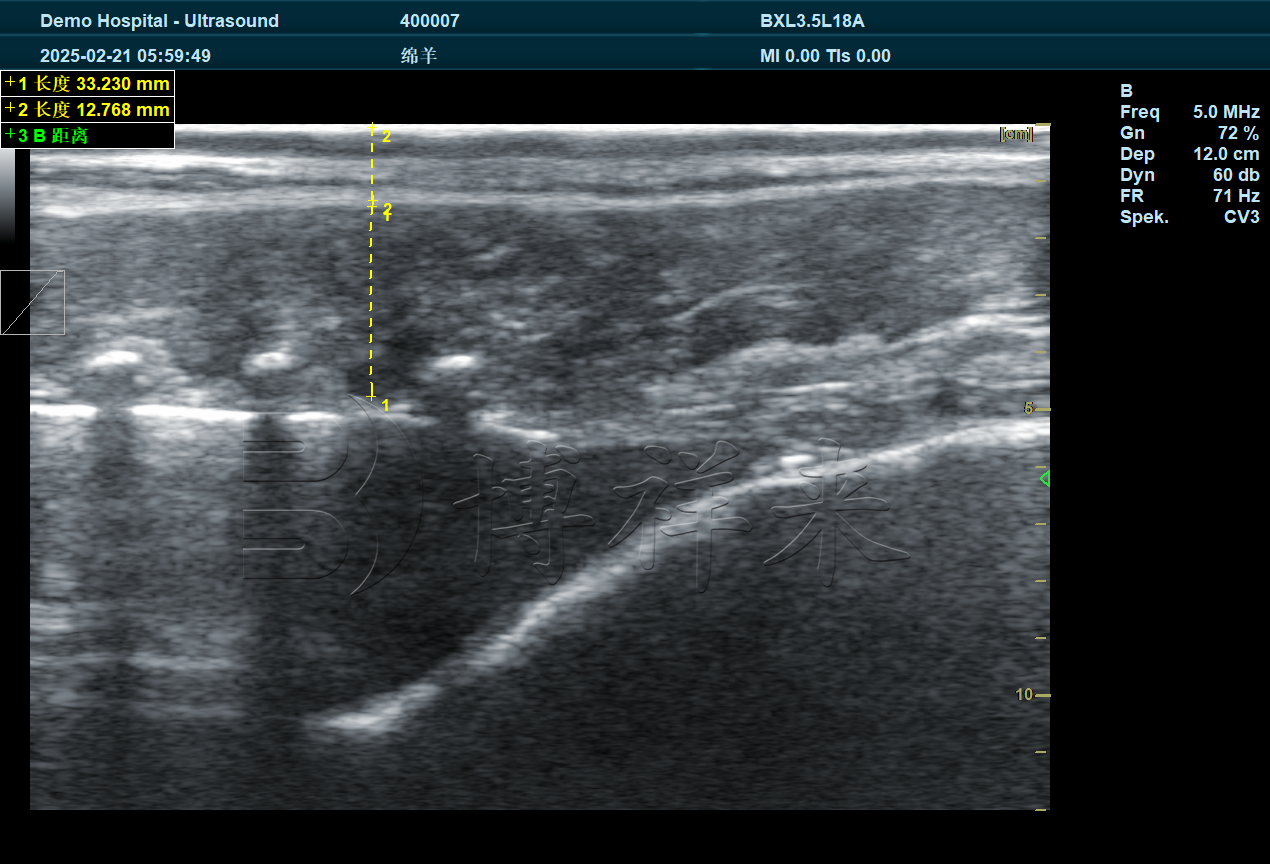

羊用背膘仪使用超声波原理,通过探头作用于肩胛后缘或倒数**肋至第二肋之间的检测区,测量皮层、脂肪层与肌肉层之间的回声差异,从而准确读出背膘厚度。

因为羊的皮肤相对特殊,超声衰减明显,一般超声设备很难得到清晰的背膘影像。而专业的羊用背膘仪会针对羊皮肤吸收特性优化频率,使脂肪层与肌肉界面更容易被分辨出来。这也是专用设备与普通B超最大的差别所在。

在一些羊毛较长的品种,如美利奴羊或绵羊,毛发只需拨开即可检测;而在毛发细短的品种中,适当剃毛能提高图像清晰度,使背膘值更准确。